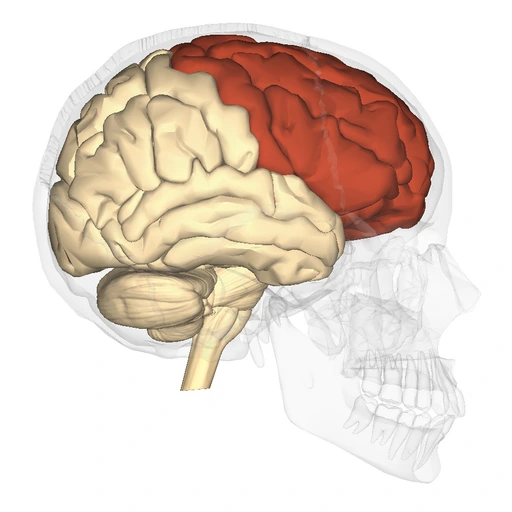

The idea that the brain drastically changes isn’t unfounded. According to Mariam Arain et al., the frontal lobe—the part of the brain responsible for a wide range of essential functions, including movement, cognition, and emotional regulation—doesn’t fully mature until around the age of 25. This late maturation is due to the brain’s “back-to-front” pattern of development, which means the prefrontal cortex is one of the last regions to fully develop.

What does that mean? Simply put, as the frontal lobe finishes developing, your brain’s “executive skills,” like judgment and decision-making, problem-solving, reasoning, impulse control, and planning, become more solid. The result? Fewer purely “gut-feel” choices, and more decisions guided by logic and reflection. A departure from the emotional volatility that most people experience in their teens and early 20s.

New research by Alexa Mousley et al. from the journal Nature Communications, however, offers some relief: it was found that the brain, more specifically your frontal lobe, is still very much in development even after the age of 25. There are five distinct “epochs” of brain organization, and the second epoch—classified as adolescence—actually stretches from ages 9 to 32. That means that 32 is actually the age where the brain finally transitions from its developmental adolescent phase into the “prime” adult phase, reaching peak efficiency and function. Of course, nothing is ever set in stone as more discoveries are made in the coming years, but this breakthrough just proves there’s no finality in the ways we continue to grow.

The frontal lobe controls essential cognitive tasks, including long-term planning, emotional regulation, logical reasoning, impulse control, decision-making, and general executive processing within the human brain.